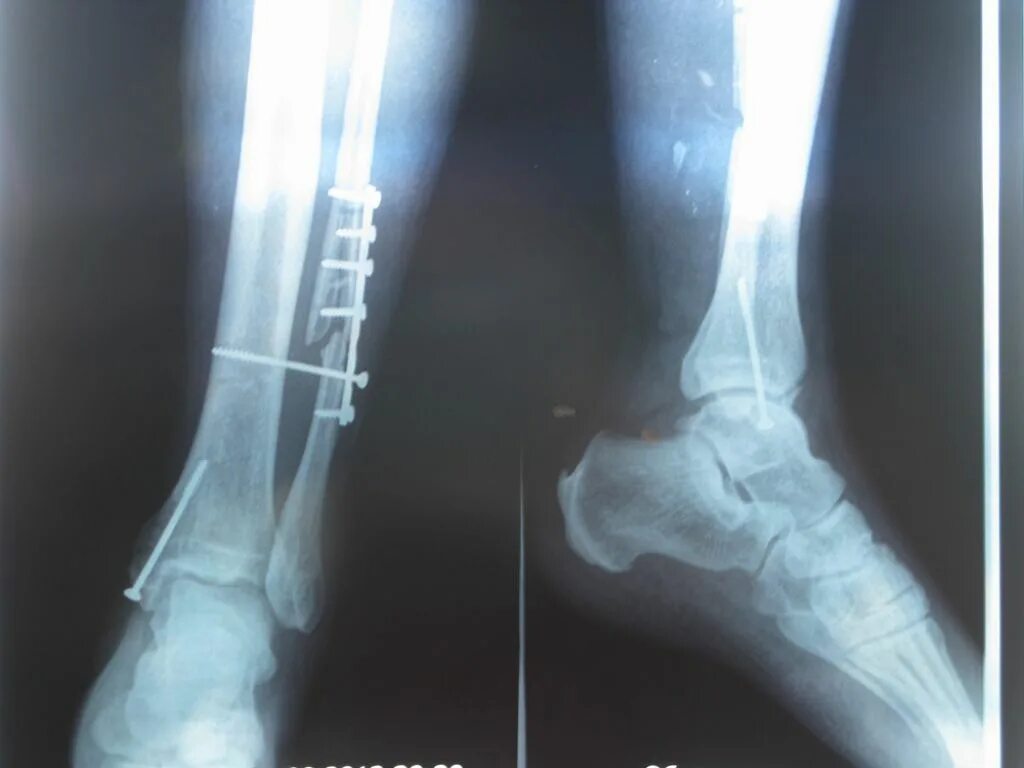

Сколько срастается стопа